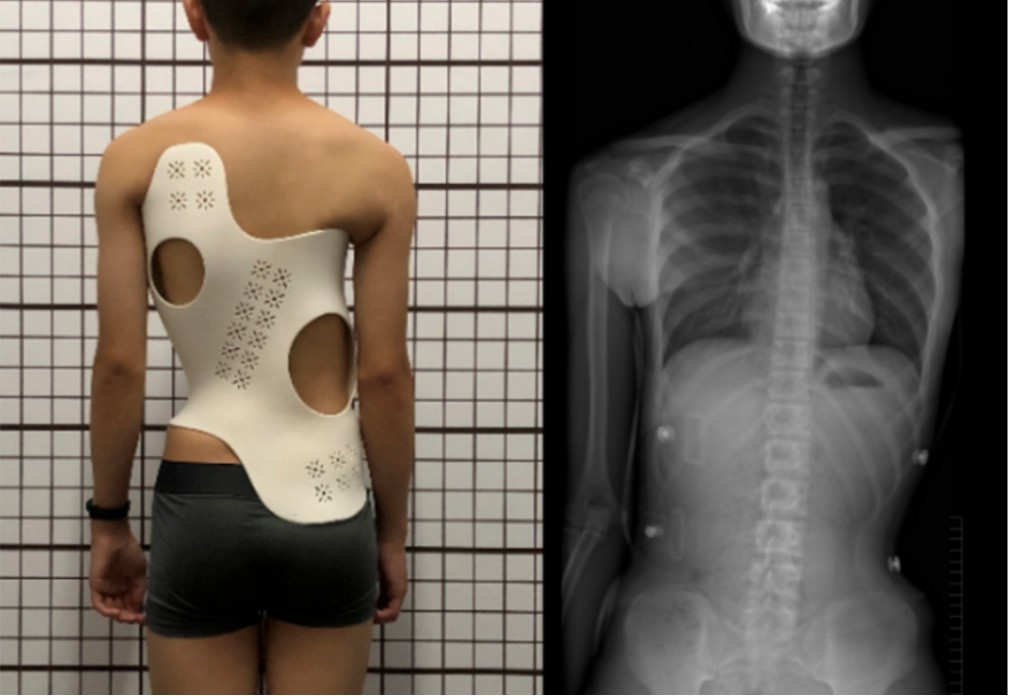

陈医生为小清查体时发现,她的脊柱棘突序列存在弯曲,并非正常的垂直排列。为进一步明确情况,医生立即安排了脊柱全长位 X 片检查。结果显示,小清的问题主要集中在胸腰段,脊柱侧弯角度约45°,属于典型的青少年脊柱侧弯,程度已需要进行手术干预。

在与吴女士充分沟通手术的利弊,并通过术前检查排除手术禁忌后,陈医生带领团队为小清实施了脊柱侧弯矫形术。术后效果显著:小清的脊柱整体恢复直立,侧弯角度矫正至10°以内,身高也增加了5厘米,久违的笑容重新回到了她的脸上。

例如侧弯角度20°以内的轻度患者可通过姿势纠正、运动的方式进行改善。侧弯角度20°-40°的中度患者则需要通过使用支具进行矫正。侧弯角度45°以上的严重患者则需要手术矫形。